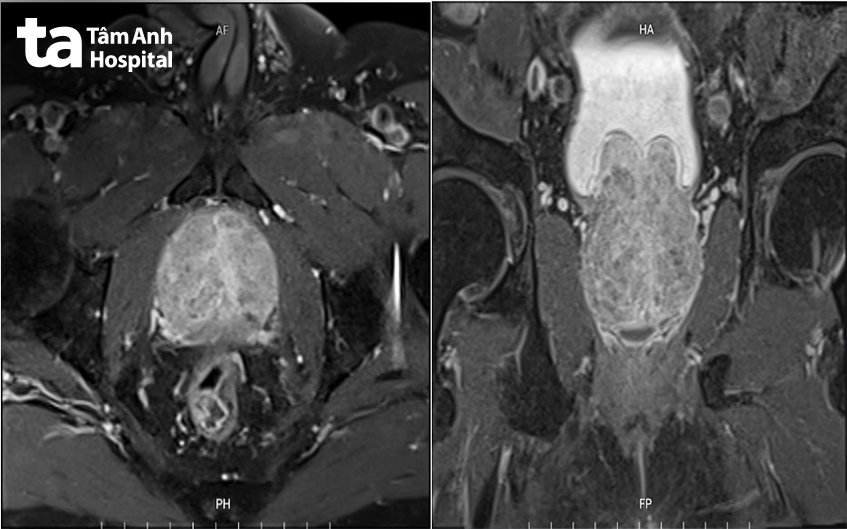

Sau khi siêu âm và chụp cắt lớp vi tính (CT 768 lát cắt) bụng, loại trừ các nguyên nhân tiểu máu từ thận, niệu quản và bàng quang, các bác sĩ chẩn đoán nguyên nhân tiểu máu do phì đại tuyến tiền liệt lành tính. Thể tích tuyến tiền liệt của người bệnh là 117 ml, gấp 4,5 lần kích thước tiền liệt tuyến của người bình thường (khoảng 25 ml). Các mạch máu tăng sinh để nuôi tuyến tiền liệt bị vỡ, và người bệnh tiểu khó, phải rặn làm trầy xước niêm mạc bàng quang dẫn đến tiểu máu.

Ông V. có chỉ định can thiệp cầm máu, loại bỏ vùng tăng sinh. Tuy nhiên, vùng tăng sinh quá lớn và sức khỏe người bệnh yếu, kèm bệnh nền nặng là tăng huyết áp, tiểu đường, nhiều nguy cơ ngay cả khi thực hiện cuộc mổ nội soi. Do đó, các bác sĩ ngoại tiết niệu và can thiệp mạch đã hội chẩn, thống nhất điều trị cho bệnh nhân bằng phương pháp can thiệp nội mạch nút động mạch tuyến tiền liệt hai bên siêu chọn lọc.

Cũng bị phì đại tuyến tiền liệt nhưng vùng tăng sinh của ông L.H. (68 tuổi, Long An) không chỉ chèn ép niệu đạo mà còn lồi nhiều vào lòng bàng quang, làm giảm thể tích bàng quang. Tình trạng này khiến ông H. mỗi đêm phải đi tiểu 5-6 lần (bình thường chỉ 1 lần), ảnh hưởng tới giấc ngủ, sức khỏe. Người bệnh được chỉ định nút mạch tuyến tiền liệt hai bên siêu chọn lọc thành công.